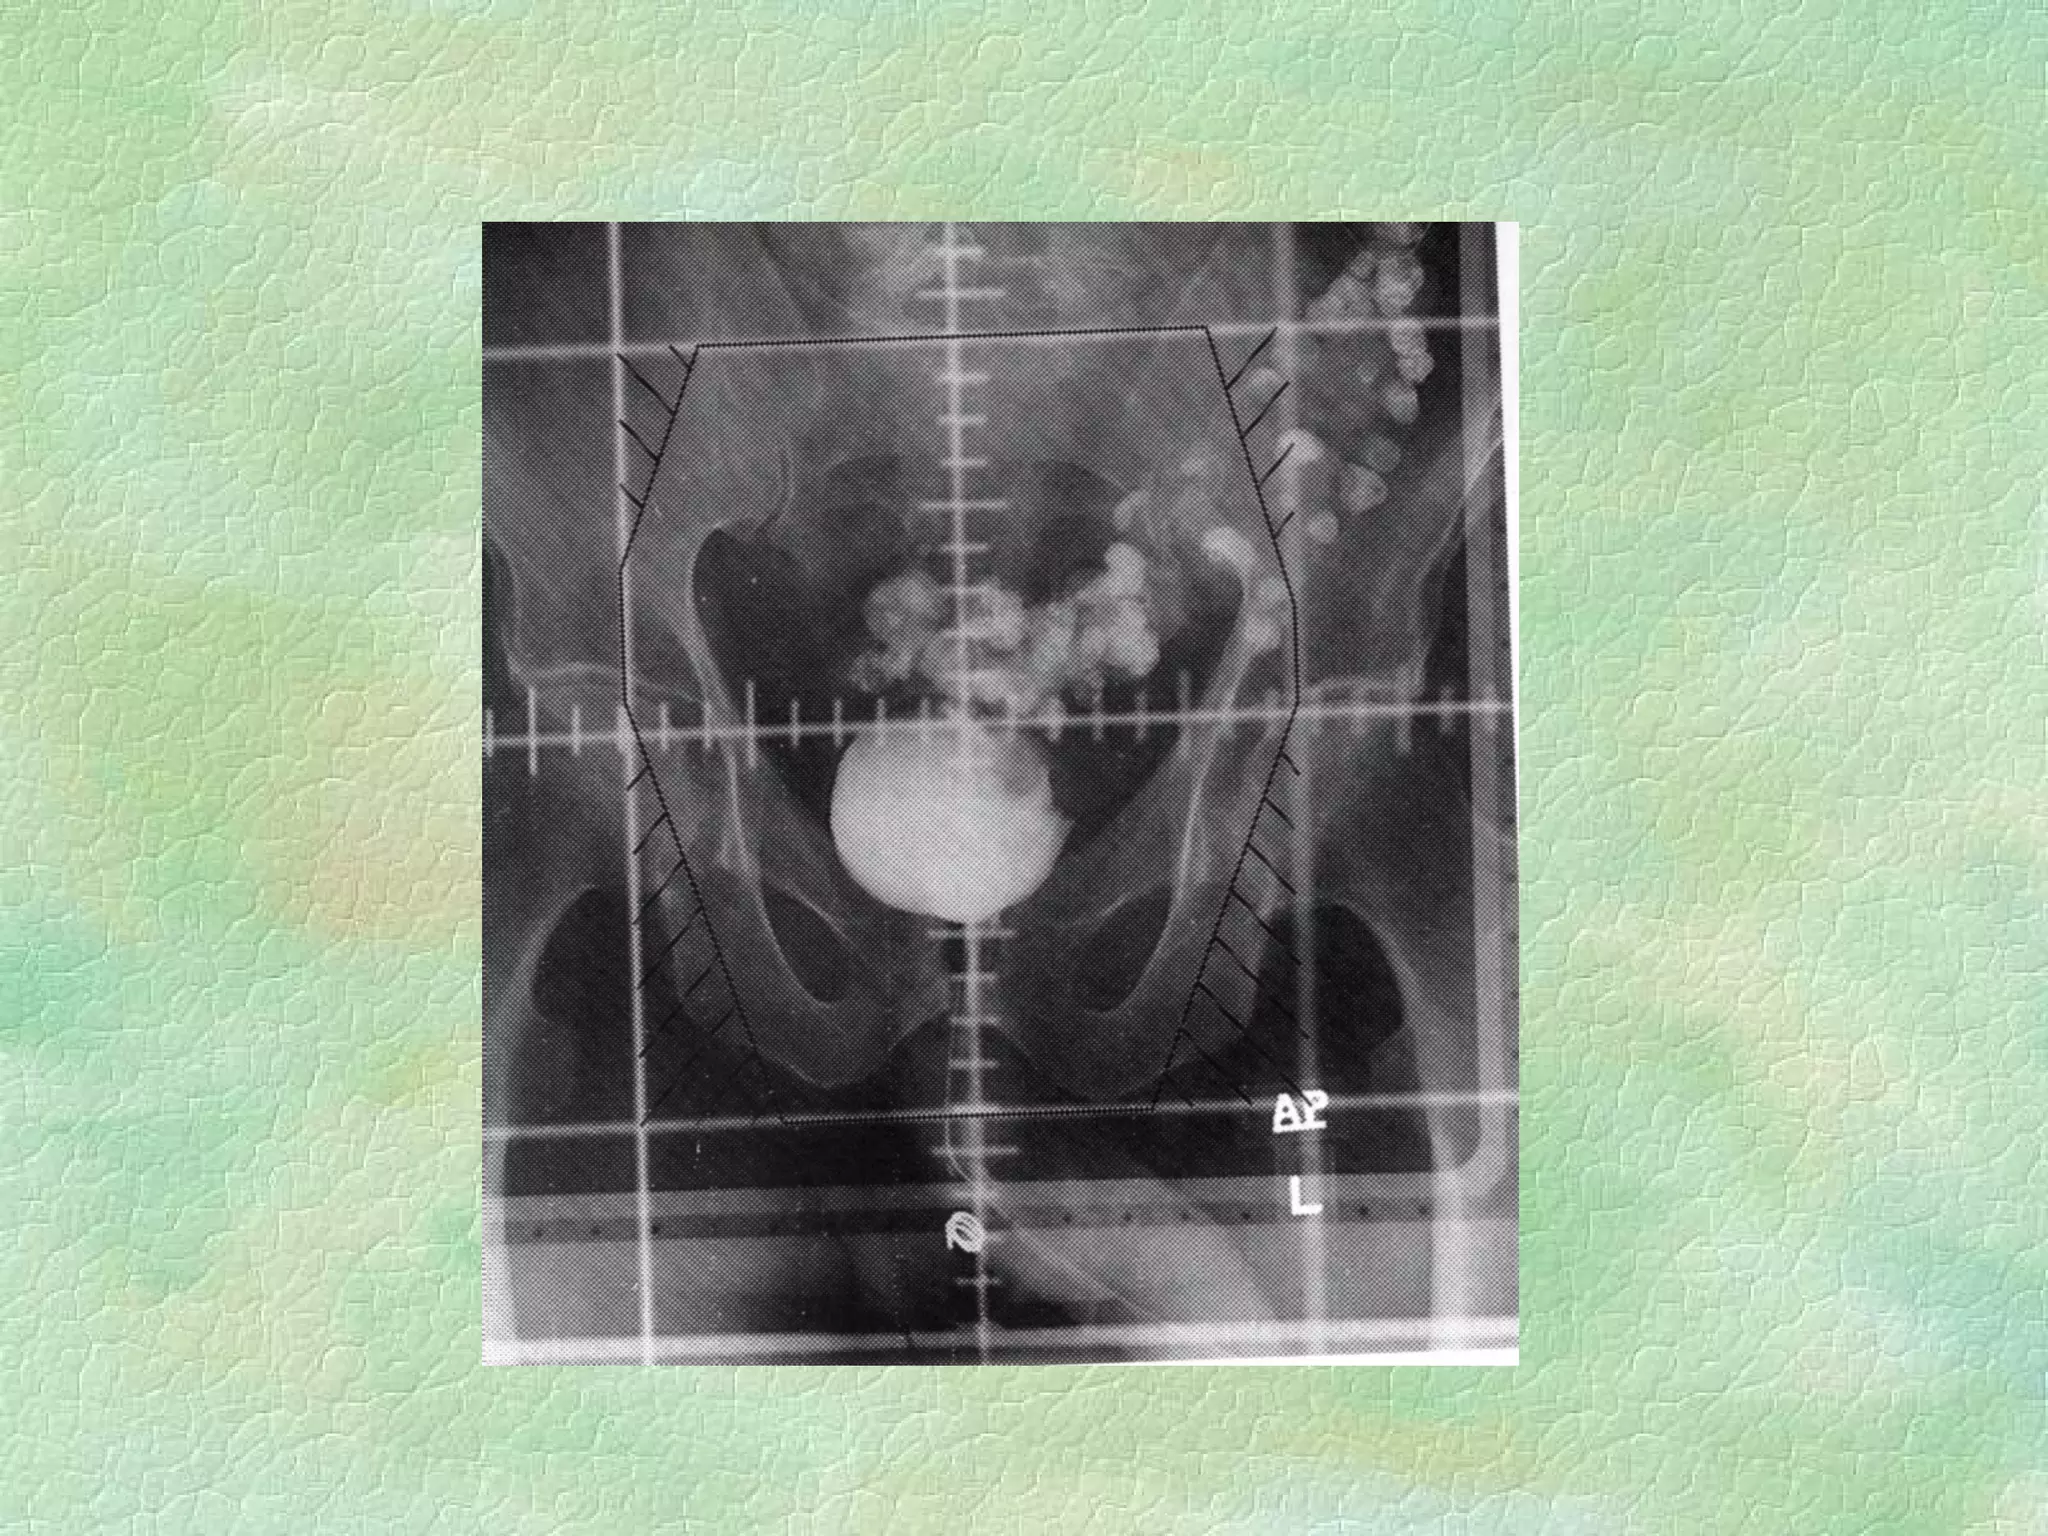

Conventional Simulation ImmobilizationDiagnostic energy X-rays replace Megavoltage beams Lower patient dose, better images, real-time fluoro External coordinate system same as treatment coordinate system

Volume Definition Externalreference palpation,visual radio-opaque markers Internal reference bony landmarks, other anatomical transfer from CT contrast agents, internal markers

Lateral Field Nodesoutlined With solder

Problems: External contoursmust be obtained for dose distribution calculation Time consuming Volume definition is difficult

Advantages: Organ motioncan be visualized on fluoro Co-localization of simulation/treatment geometries Treatment geometry problems can be avoided